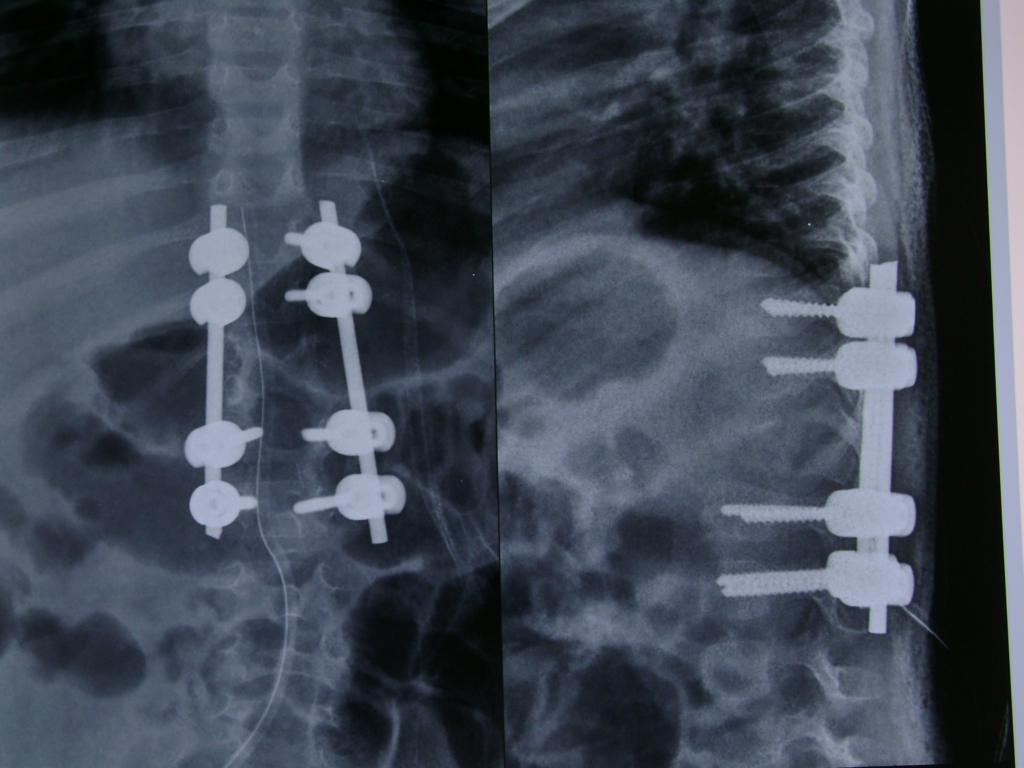

Postoperative x-rays after excision and fixation